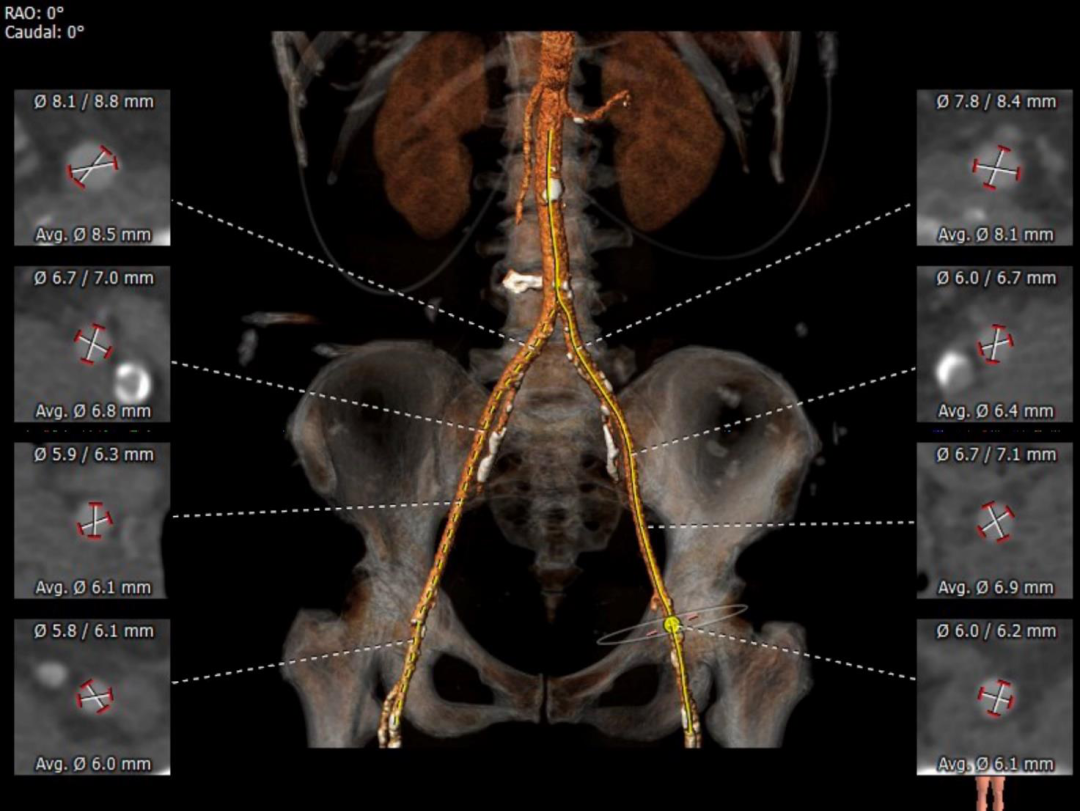

左右冠开口高度可,右冠多发钙化,依据瓦氏窦宽度和瓣叶长度预估右冠风险较小,左冠存在堵塞风险。

瓦氏窦内径、窦管交界内径偏小。升主内径尚可,主动脉瓣环与水平面夹角可,主动脉弓角度与宽度可。

双侧血管内径可,存在散在钙化,符合血管入路条件。

主动脉根部评估:

瓣环上解剖及钙化分布:

外周血管及主动脉弓解剖: